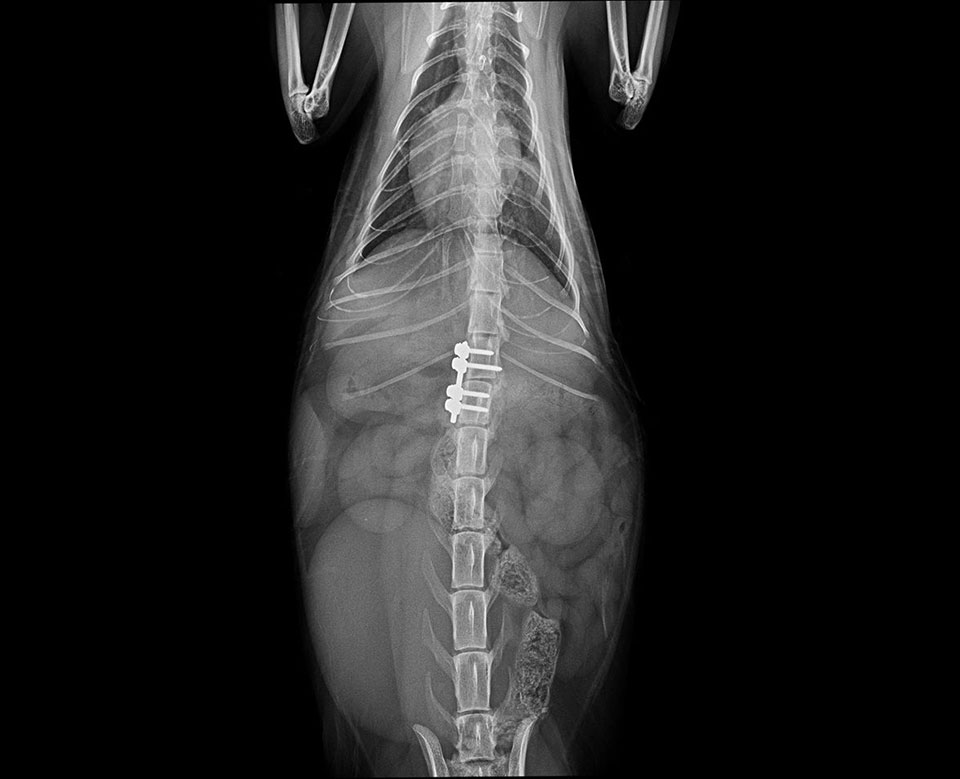

Mini SOP-LC (for 2,0mm srews) were used for stabilisation of vertebral luxation and fracture in cat.